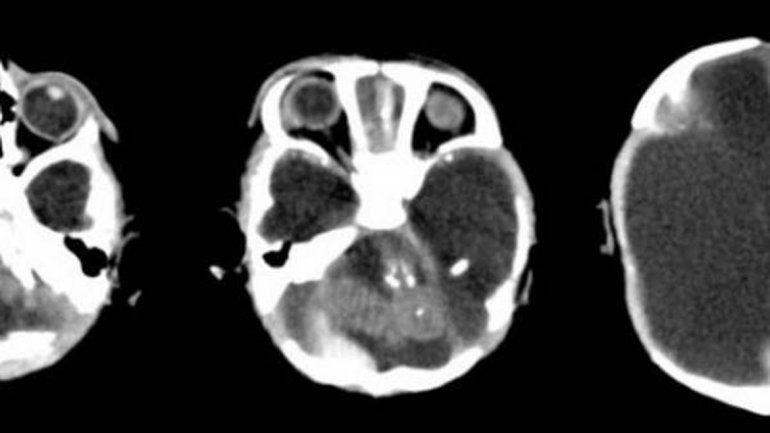

Nació un bebé con microcefalia por zika en Córdoba. La enfermedad se la transmitió la mamá, que contrajo el virus durante el embarazo, estando en Bolivia, de donde es oriunda. El virus se contagia a través de la picadura del mosquito Aedes Aegypti infectado, el mismo insecto que es vector del dengue y la fiebre chikungunya. En este caso fue una transmisión vertical, pues se dio entre la gestante y el nonato.

“Se detecta el caso y se hace la notificación a epidemiología de Córdoba y al Sistema Nacional de vigilancia epidemiológica lo que genera un alerta”, sostuvo y agregó: “Sería uno de los primeros casos de un paciente en el que en los controles de diagnósticos por imágenes se detectan ya en las primeras ecografías las alteraciones en el desarrollo neurológico”.

La funcionaria, además, precisó que en los estudios “también se encontraron otras lesiones del sistema nervioso central, que son características a los casos de microcefalia y alteraciones neurológicas vinculadas a embarazadas que padecieron de zika”.